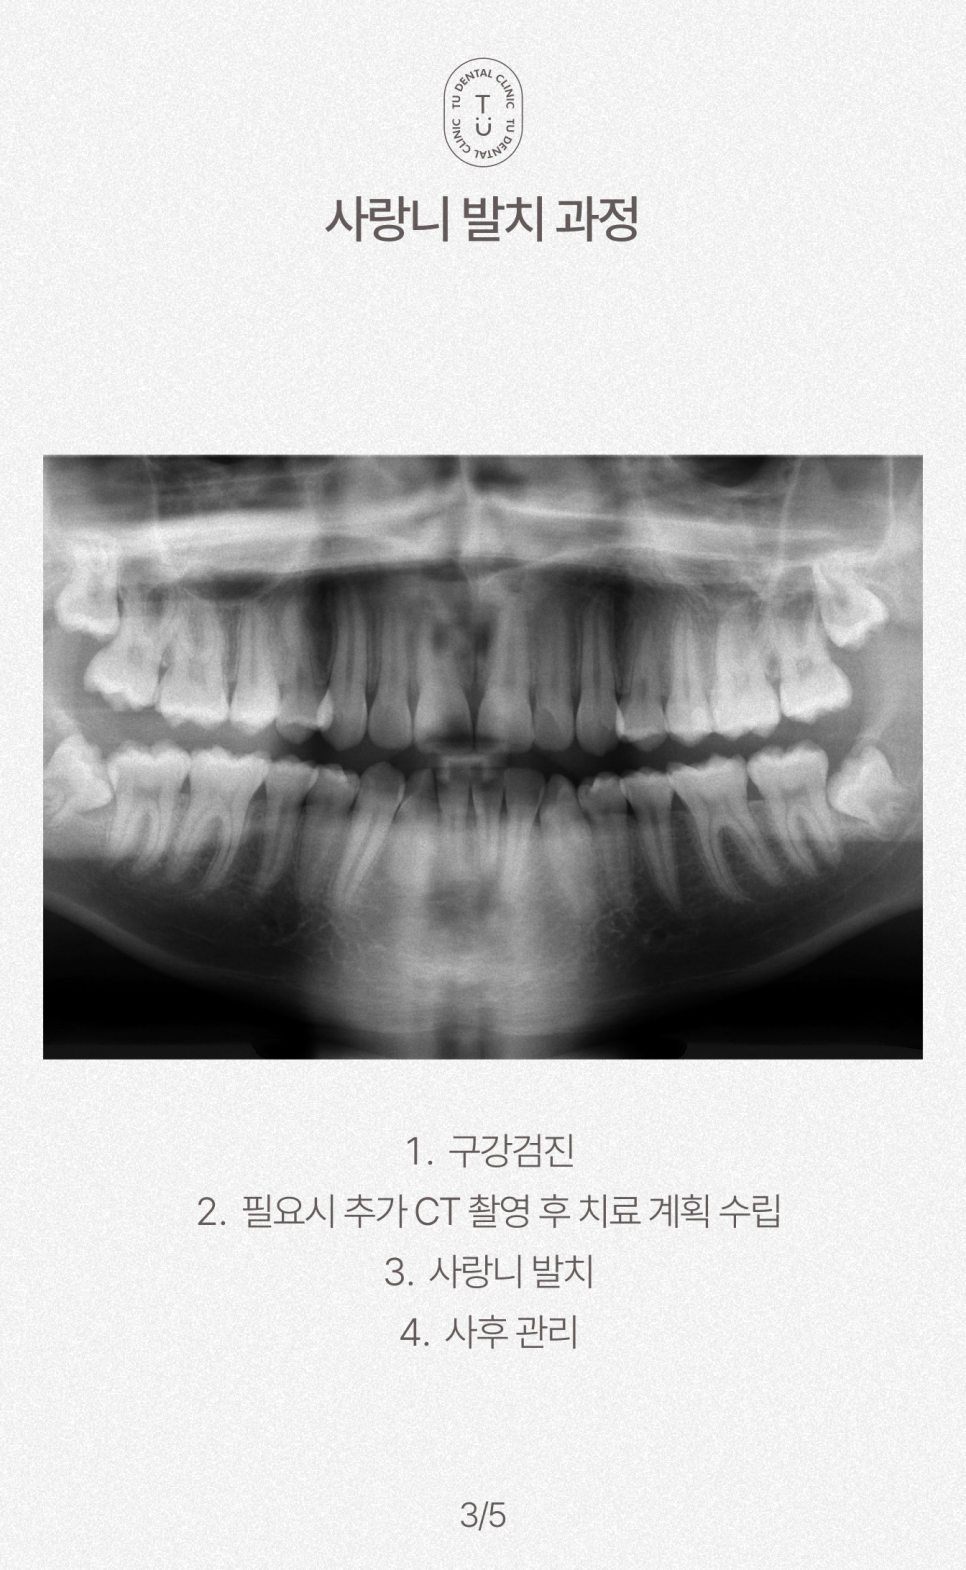

사랑니 발치 과정

티유치과(TU치과)

구강검진

필요시 추가 CT 촬영 후 치료 계획 수립

사랑니 발치

사후 관리